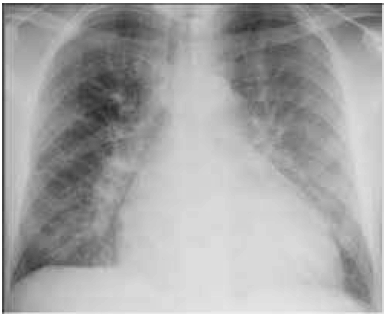

Paciente MDH, homem, de 42 anos de idade, foi internado por dispneia aos esforços há cinco meses, com sensação de opressão no tórax há uma semana. Nega tosse, expectoração ou chiado. Nega tabagismo. Seu exame físico da entrada revelou o seguinte: PA de 110 mmHg × 76 mmHg; FC de 54 bpm; saturação de O2 (ar ambiente) de 91%. Ausculta cardíaca: hiperfonese e desdobramento de segunda bulha em foco pulmonar. Turgência jugular bilateral. Pulmões com estertores bibasais. Apresenta ecocardiograma transtorácico com FEVE de 34% e a radiografia inicial mostrada a seguir. O paciente é estabilizado no terceiro dia da internação e já está com a volemia estável.